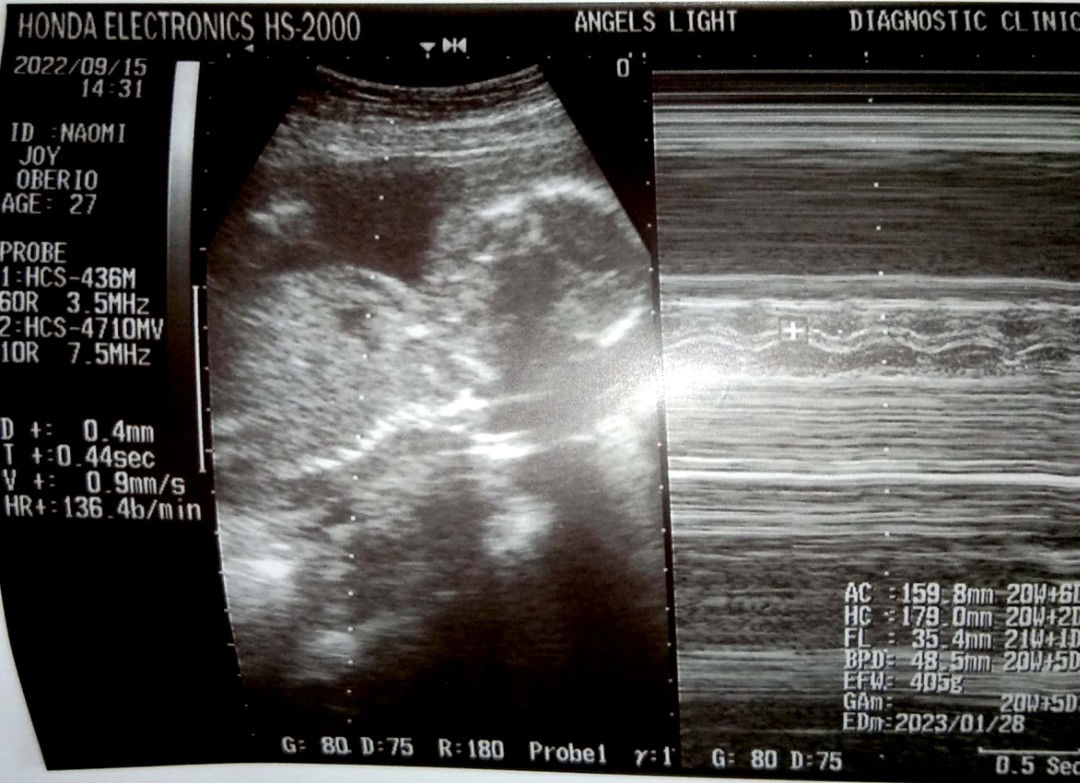

mliit po b sya s 2.493 grams ano po b normal weight nya dapt